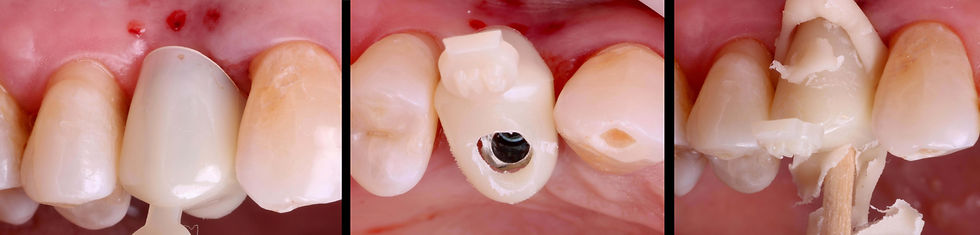

Positioning of a titanium temporary engaging post and following reduction in height according to the occlusal plane.

Adjustment and relining of the temporary crown with Reef resin on the reduced post, keeping the screw hole free. GO TO THE VIDEO

Finishing and polishing of the temporary crown that closes on the post, to leave space for the tissues so that they can heal and thicken.